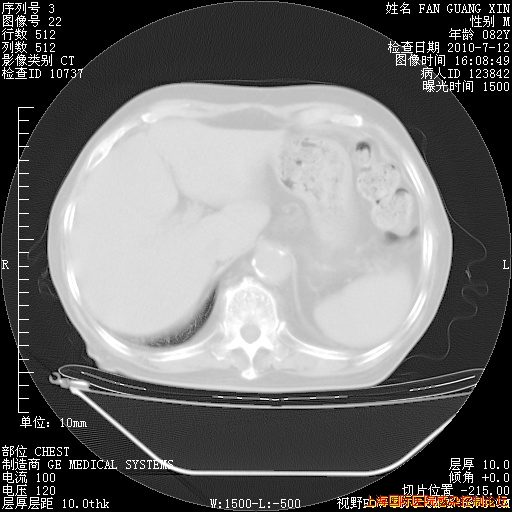

今天复查CT

今天CT

整整相隔30天的肺部CT好像有所好转啊。甲强龙减量第3天,需要观察体温。

海管,自昨日你和我通完话后,不知您岳父消化道症状有无缓解?体温怎样?阅读7.12日胸部ct,个人认为目前激素治疗是有效的,甲强龙减量是适宜的。因在抗痨治疗,需密切观察肝功、肾功能和血常规。不过,老年、长期住院和大量使用激素,很担心菌群失调发生